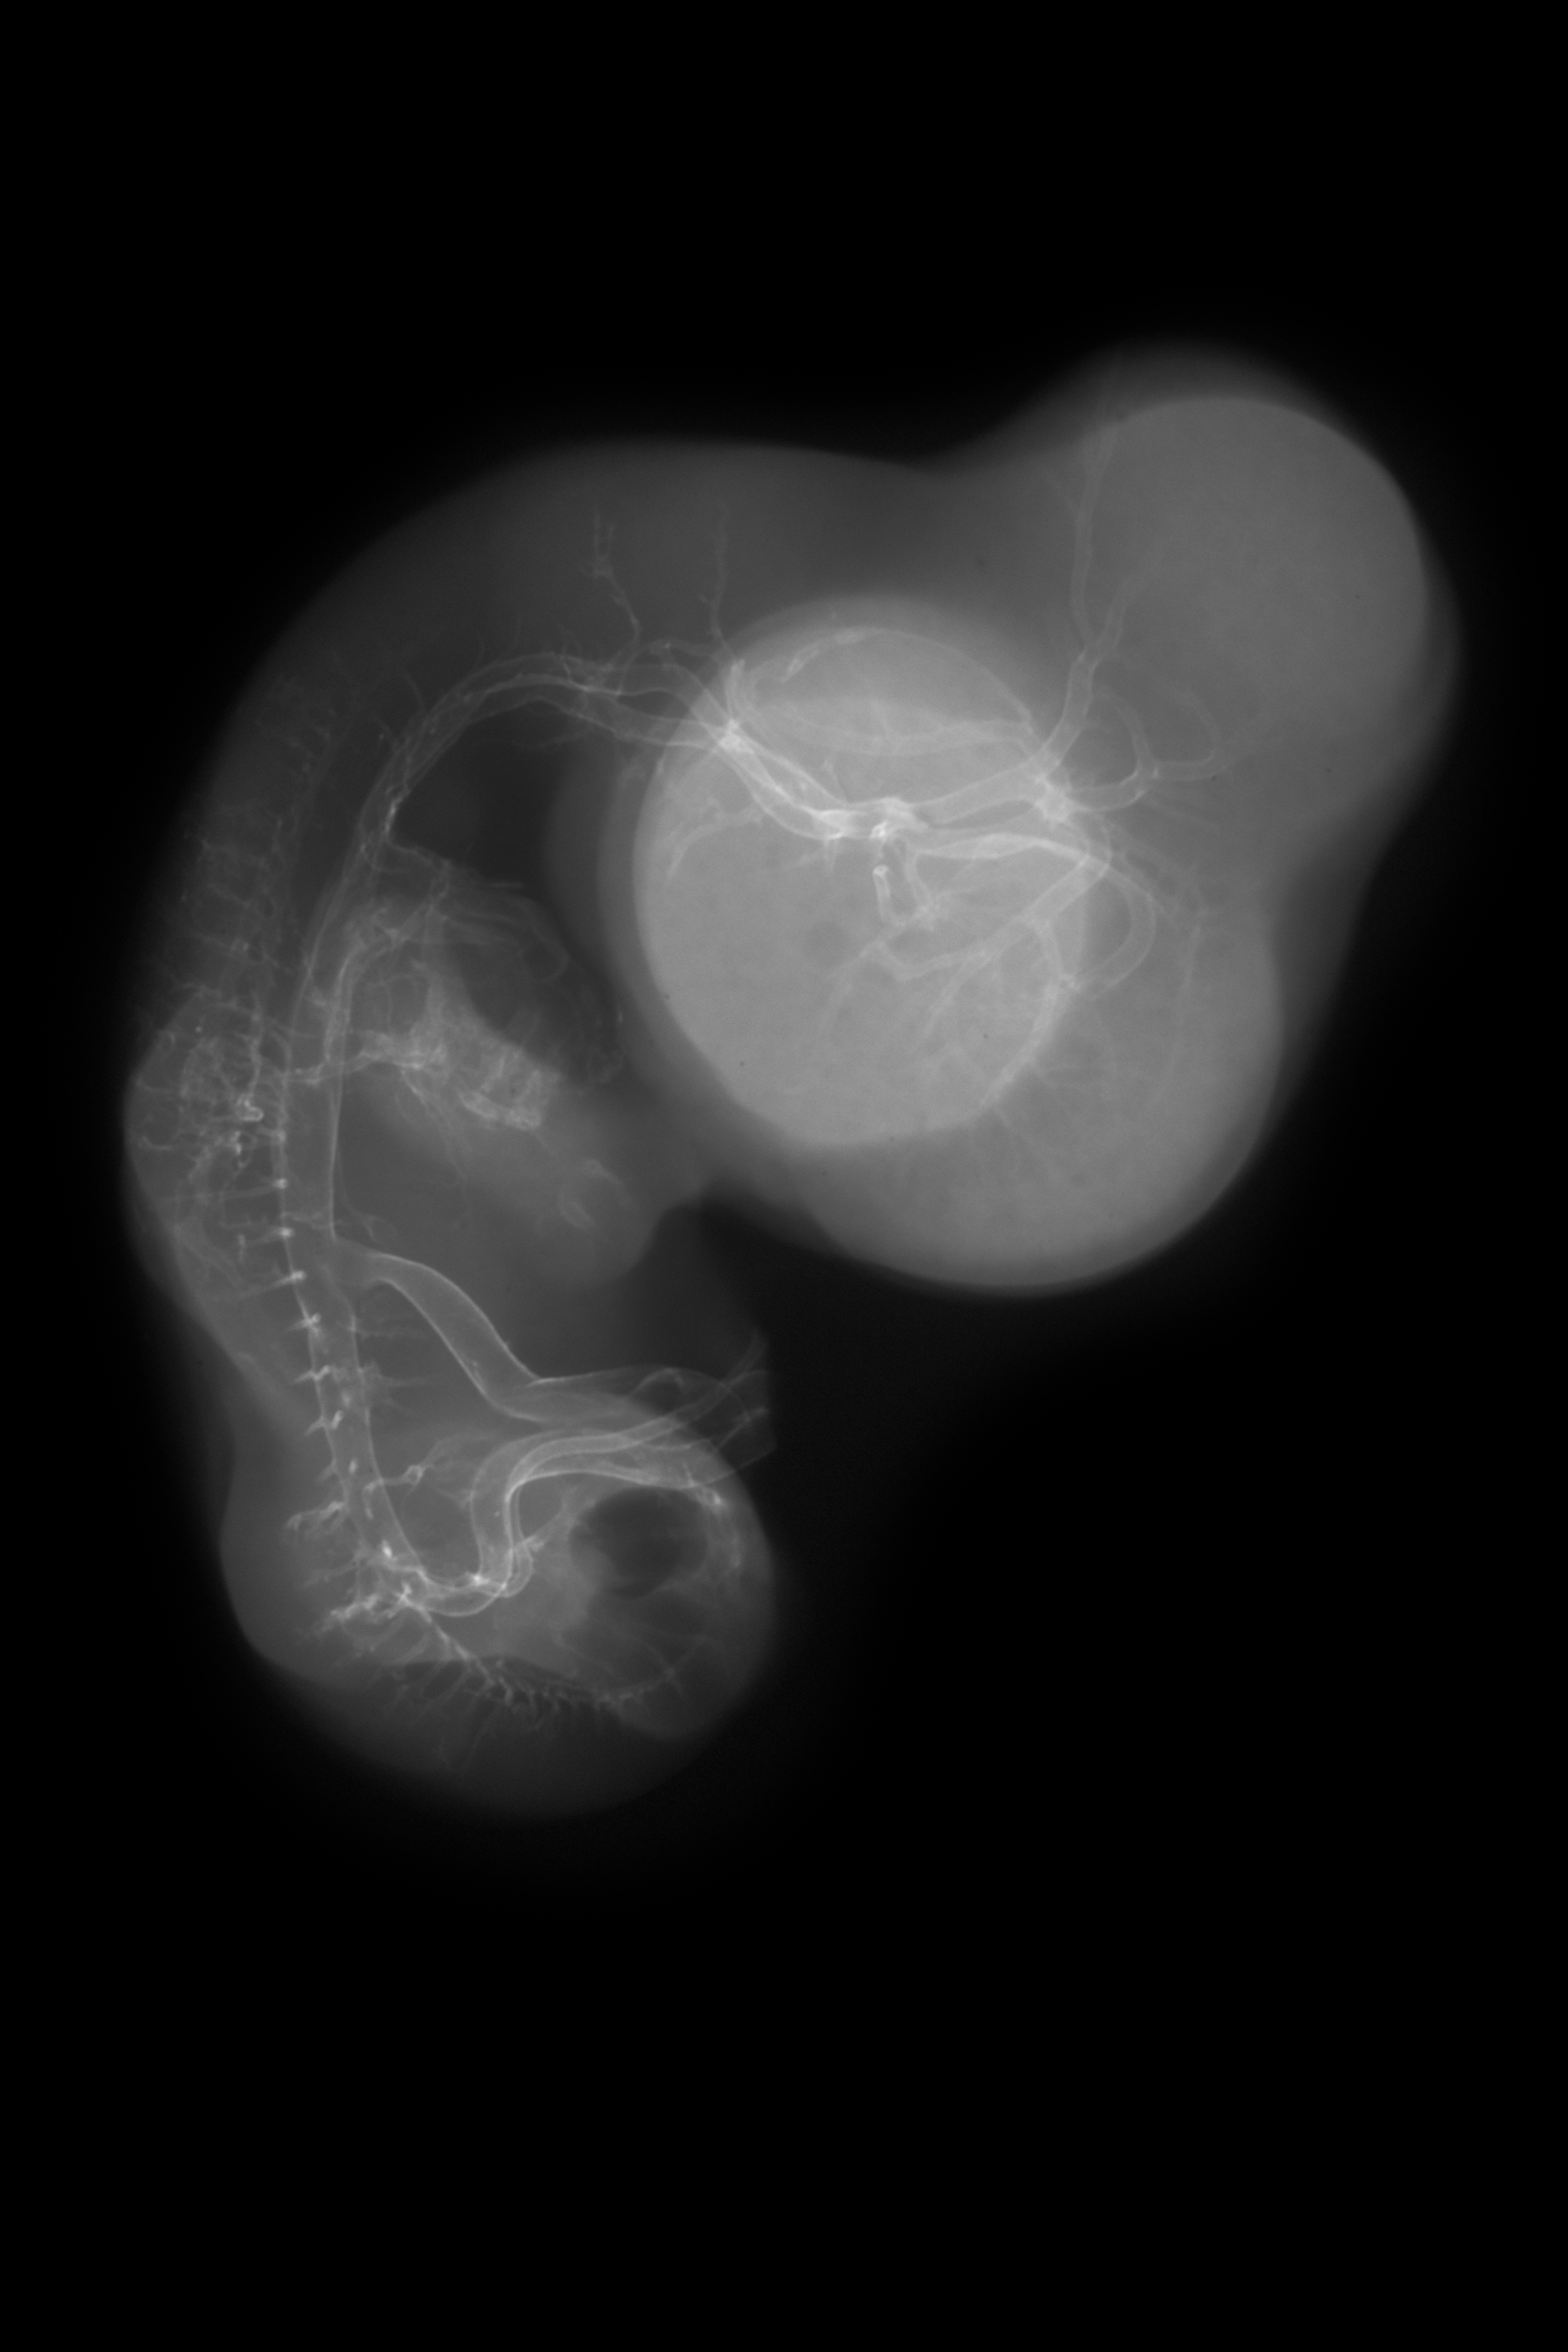

Hamburger-Hamilton (HH) Stage 29 (approx. 6 - 6.5 days)

X-Ray Micrographs